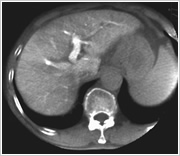

こちらの検査室では、立体的な血管像やCTのような画像を作成することができ、診断や治療の確認に利用していきます。

CTのような断層の画像を表示することもできます。